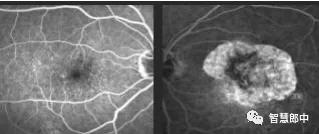

干性黄斑变性的眼底血管造影(右眼) (左眼)